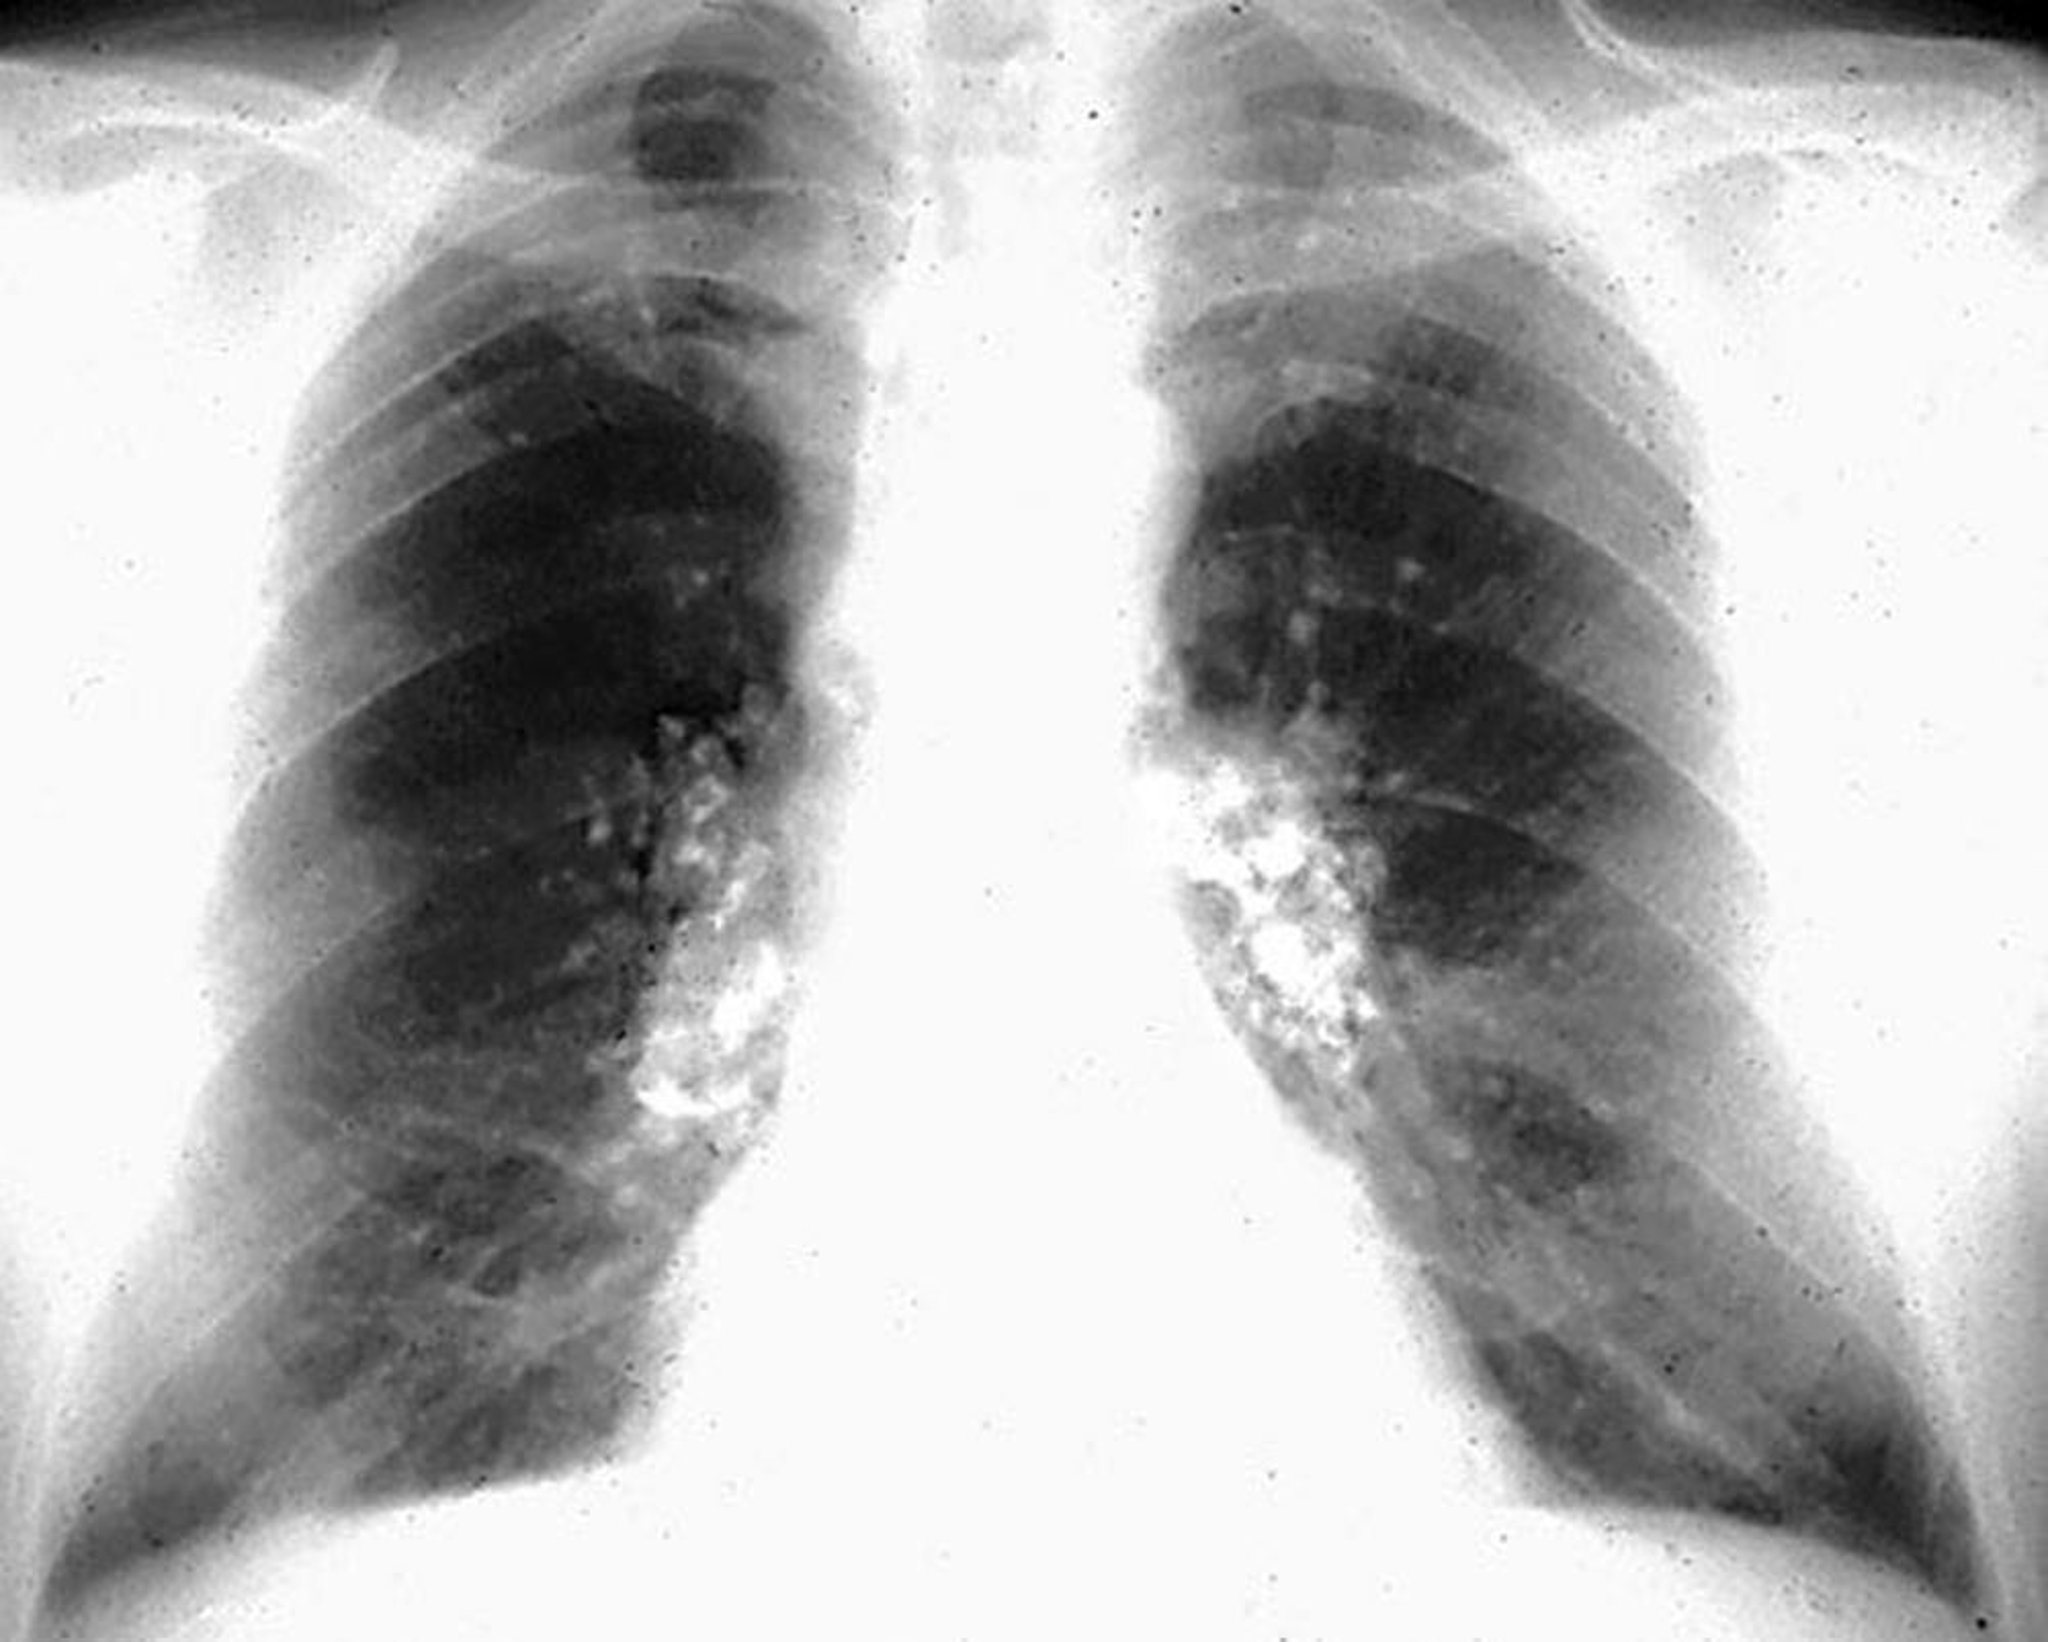

Silicosis: calcificaciones en cáscara de huevo

Image courtesy of David W. Cugell, MD.